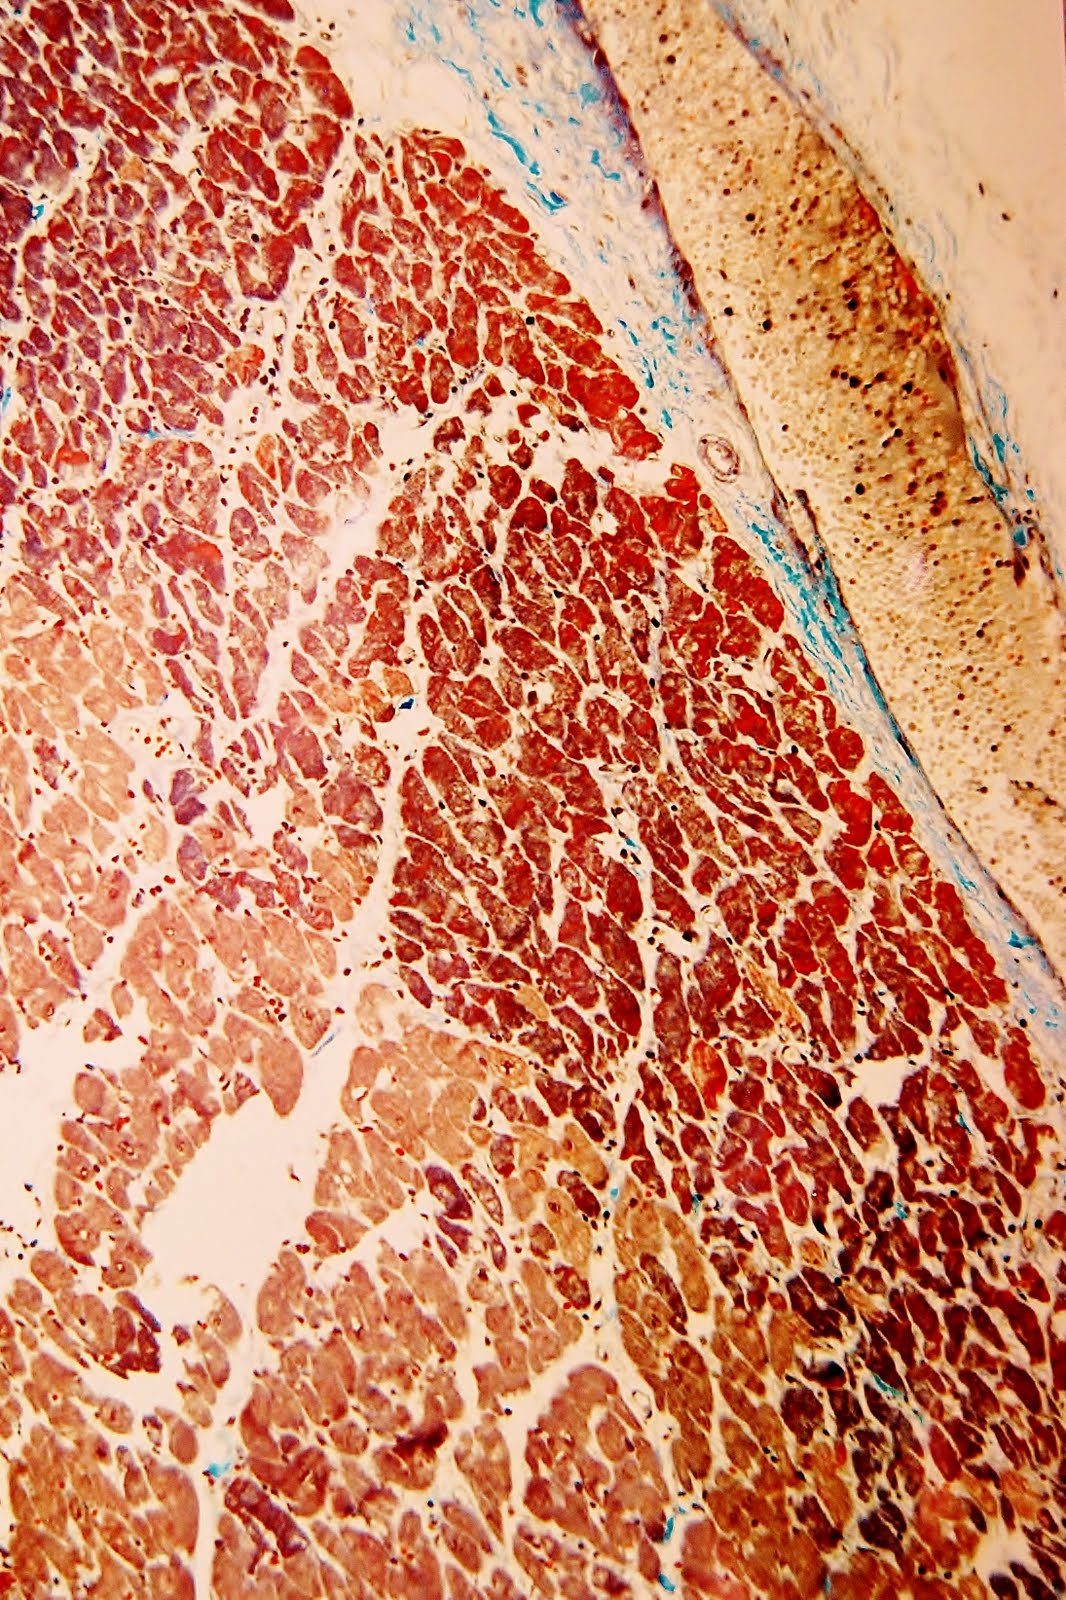

Corazón.-

De 370 g, post-fijación. Discreta hipertrofia ventricular derecha e hipertrofia ventricular izuierda de tipo hipertensivo. Las arterias coronarias descendente anterior e izquierda circunfleja presentaban estenosis segmentaria ateromatosa, de grado marcado a severo (75-95% de reducción del calibre luminal).Signos morfológicos compatibles con aplicación de desfibrilador en epicardio y endocardio. Numerosas fibras rojas expresivas de anoxia-isquemia miocárdica.

Pulmón.-

Edema alveolar masivo. Pulmón de fumador pesado.

Granulomatosis pulmonar narcodependiente.